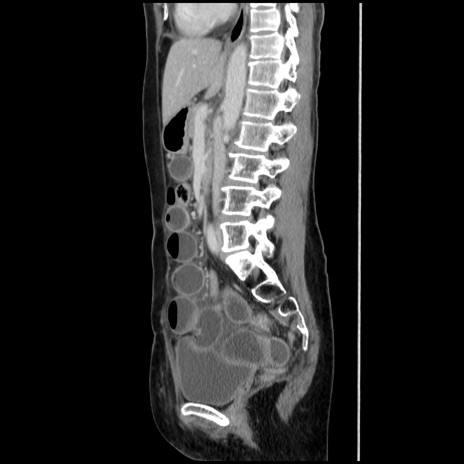

症例32(矢状断像)

【症例】40歳代 女性

【主訴】上腹部痛、嘔気・嘔吐

【現病歴】約9時間前頃から急に上腹部痛、嘔気、嘔吐が出現。改善しないため救急要請。

【既往歴】子宮頚癌(広汎子宮全摘術、放射線療法)、腸閉塞

【身体所見】腹部:平坦、軟、腸雑音亢進、上腹部を中心に腹部全体に圧痛あり。

【データ】WBC 8400、CRP 0.03